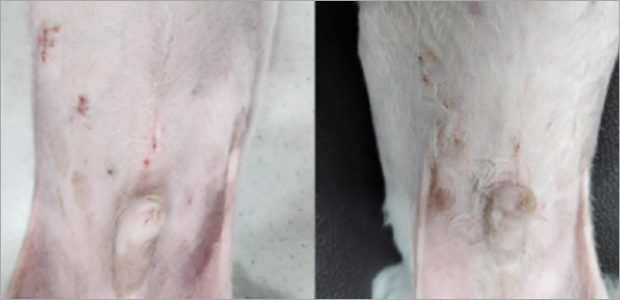

복강경 여아 중성화 수술

우리 아이가 생애 처음하게 되는 수술이 중성화 수술인 만큼, 환자가 덜 고통받기를 바라며 복강경 중성화를 알아보고 오시는 보호자분들이 많아졌습니다.

복강경을 사용하면 일반적인 암컷 강아지 중성화처럼 배를 여는 개복 수술을 하지 않고 복강경 장비가 들어갈 수 있는

1cm 이내의 작은 절개창을 2개 내어서 환자의 고통을 최소화하고 빠른 회복이 가능합니다.

예은외과센터는 베테랑 일반외과 전공 수의사가 국내 최고 복강경을 이용한 중성화로 덜 아프게수술합니다.

케이스1

- 수술 2주차

케이스2